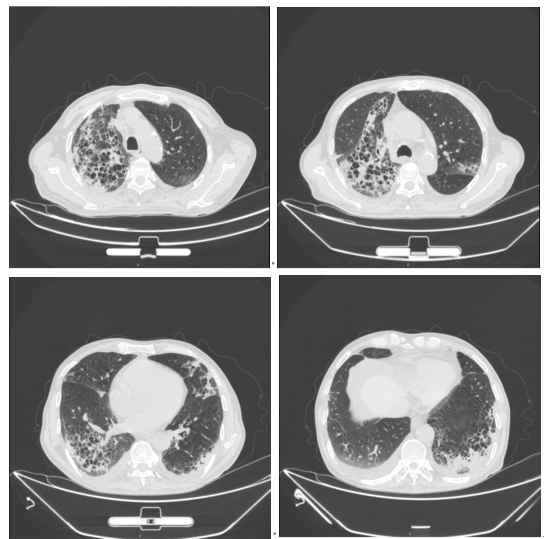

根据社区获得性肺炎治疗指南,患者入院后我们经验性使用帕拉西林钠他唑巴坦钠和莫西沙星抗感染治疗。入院第六天我们通过mNGS检测出患者的血液和痰液中存在羊流产衣原体,可确认为肺炎的病原体。但是由于衣原体感染大多都是混合感染,因此我们并没有停止帕拉西林钠他唑巴坦钠的使用。在治疗第10天,我们复查了胸部CT,结果示两肺间质性炎症较前改善,两肺少量胸腔积液(图2)。

图片

图2:入院第十天胸部CT,两肺间质性炎症较前改善,两肺少量胸腔积液

胸部CT:两肺间质性炎症,两肺肺气肿(图3)。

图3:出院第二十天胸部CT,两肺间质性炎症,两肺肺气肿。